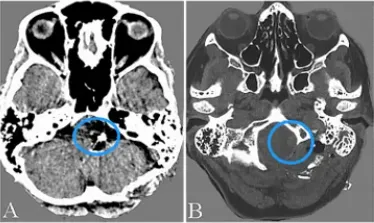

然而,术后第11天,随访CTA显示对侧VADA无症状扩大(图3c-d)。教授通过外侧枕下入路近端夹断右侧VADA(图4)。同时,通过颞下入路进行颞浅动脉-小脑上动脉旁路术,以保持后循环中的脑血流(图5)。术后双侧VADA被切除,康复后约1个月出院且术后1年随访期间病情平稳。

图3c-d:(c)术后第11天CTA显示右侧VADA迅速增大(箭头);(d)右侧椎血管造影侧视图显示右侧VADA远端延髓动脉穿孔(箭头)和大脑后动脉的前交通段发育不良。